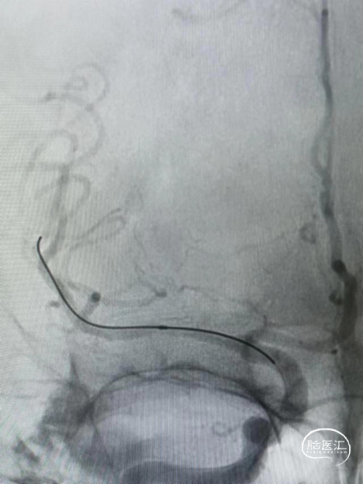

术后影像及检查

术后正位造影。

术后侧位造影